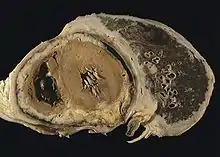

Diffuse pleural mesothelioma with extensive involvement of the pericardium.